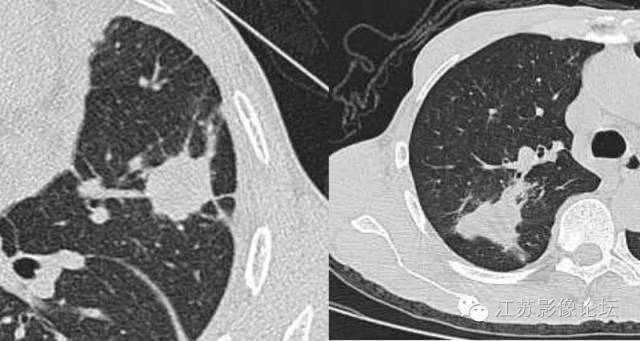

弦距与距长之比>2/5为深分叶;肺癌常见深分叶,错构瘤及结核球可呈浅分叶;炎性假瘤多呈不规则形状。